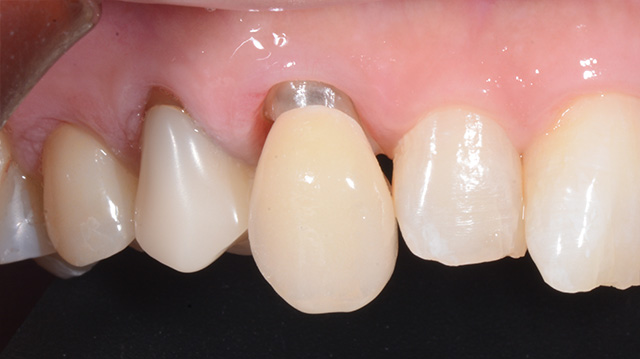

| 年代・性別 | 50代 男性 |

|---|---|

| 主訴 | インプラントをしたいが他の歯医者では難しいからと断られた |

| 治療期間 | 約1年 |

| 費用 |

仮歯 5,500円 ジルコニアクラウン 176,000円 インプラント 300,000円 インプラント仮歯 22,000円 サージカルガイド 70,000円 |

*キャンセルポリシーをご一読のうえご予約ください